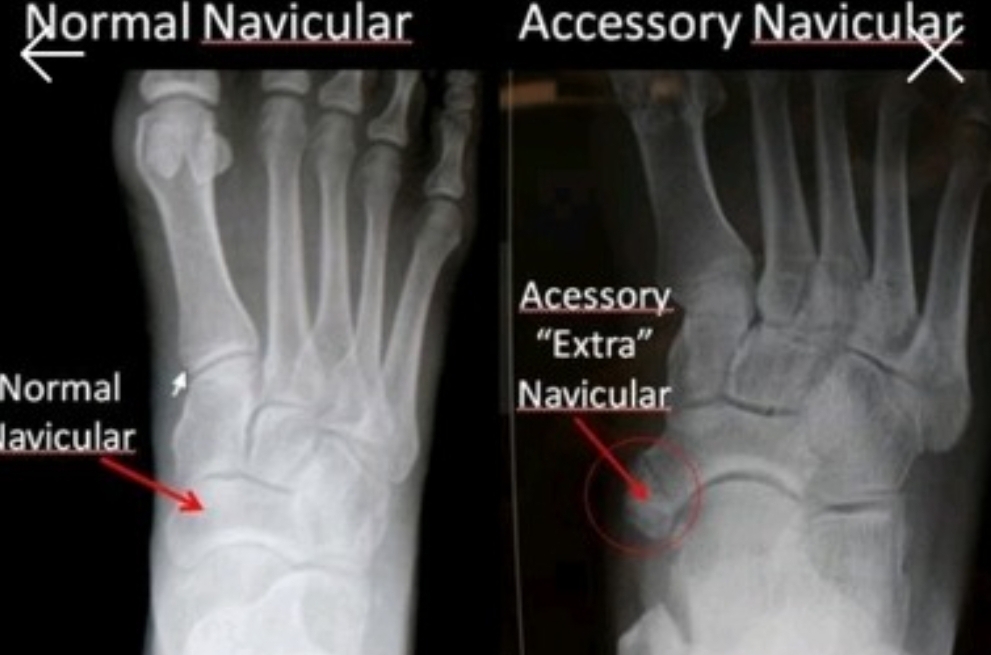

복사뼈 밑 2cm 아래에 위치한 뼈(부주상골)에 통증이 생기는 질환으로 청소년기 대표적인 족부 질환 중 하나입니다. '액세서리 뼈'라고도 불리는 부주상골은 발목과 엄지발가락을 이어주는 주상골 옆에 위치해 어느 정도 식별이 가능합니다.

이곳에 발생하는 부주상골증후군은 출생 시 뼈가 정상적으로 유합 되지 못해 나타나는 질환으로, 보통 10명 중 1명꼴로 발견됩니다. 증상은 뼈가 발달하는 시기인 13~15세 사이에 흔히 나타나는데 일상생활에서는 크게 불편함이 없어 상태를 잘 파악하지 못합니다. 그러나 농구나 발레, 인라인 스케이트처럼 발에 지속적인 압박이 가해지는 운동을 할 경우 부주상골이 눌려 통증과 부종이 생길 수 있습니다.